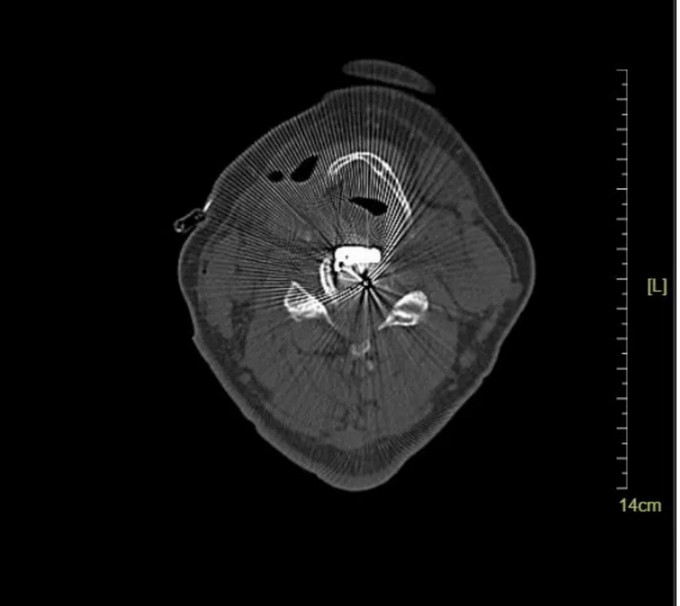

颈椎MRI横断位

入院影像学检查示:

C4-5、C5-6椎间盘突出伴钙化,C4-5、C5-6 层面脊髓变性。

术前影像